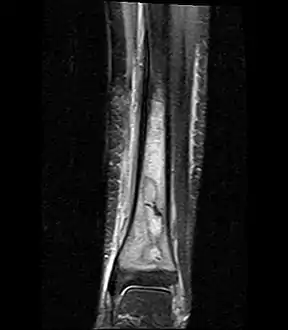

a,b) MRI showing the Brodie's abscess in the left proximal femur

A Brodie abscess is a subacute osteomyelitis, which may persist for years before progressing to a chronic, frank osteomyelitis. Classically, this may present after progression to a draining abscess extending from the tibia out through the skin. Occasionally acute osteomyelitis may be contained to a localized area and walled off by fibrous and granulation tissue.

Oval, elliptical, or serpentine radiolucency usually greater than 1 cm surrounded by a heavily reactive sclerosis, granulation tissue, and a nidus often less than 1 cm. The margins often appear scalloped on radiograph. Brodie's abscess is best visualized using computed tomography (CT) scan. Associated atrophy of soft tissue near the site of infection and shortening of the affected bone. Osteoblastoma may be a classic sign for Brodie's abscess.